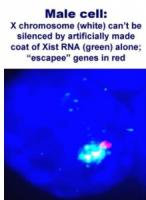

MALADIES liées à l'X: Pourquoi l'un parle et l'autre pas